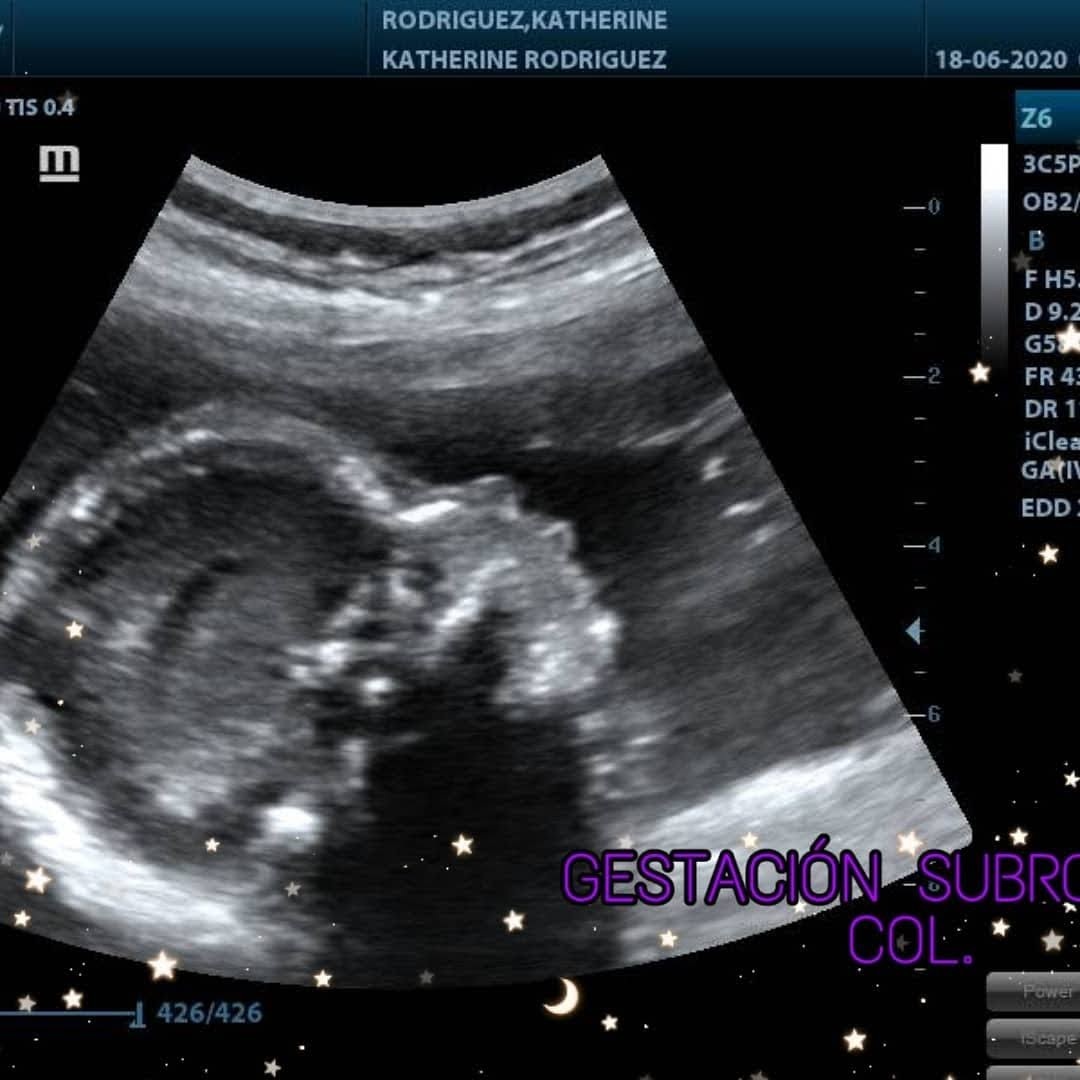

ULTRASON